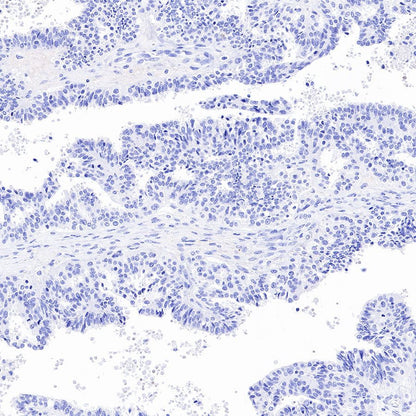

Immunohistochemistry

Negative control: IHC shows negative staining in paraffin-embedded human ovarian cancer. Anti-PSA antibody was used at 1/1000 dilution, followed by a HRP Polymer for Mouse & Rabbit IgG (ready to use). Counterstained with hematoxylin. Heat mediated antigen retrieval with Tris/EDTA buffer pH9.0 was performed before commencing with IHC staining protocol.